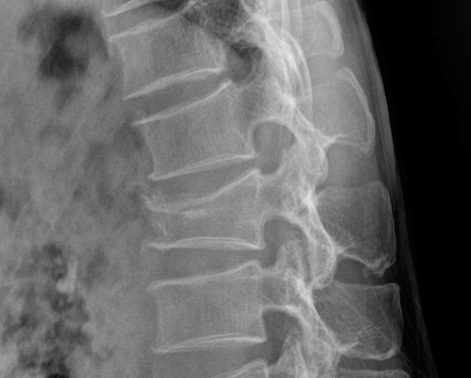

척추압박골절은 척추의 뼈가 압박되어 발생하는 부상으로, 다양한 원인에 의해 나타납니다. 특히 노인층에서 흔히 발생하지만, 젊은 사람들도 예외는 아닙니다. 이 글에서는 척추압박골절의 주요 원인에 대해 살펴보겠습니다.

심한 통증이 지속되거나 골절이 심각한 경우, 수술적 치료가 필요할 수 있습니다. 가장 일반적인 수술은 척추 성형술(Vertebroplasty)과 후방 경유 척추유합술(Kyphoplasty)입니다. 척추 성형술은 골절된 부위에 의료용 시멘트를 주입해 뼈를 고정하는 방법입니다. 후방 경유 척추유합술은 성형술과 비슷하지만, 풍선을 삽입해 골절된 척추뼈를 높인 후 시멘트를 주입하는 방식으로, 더 심한 골절에 사용됩니다.